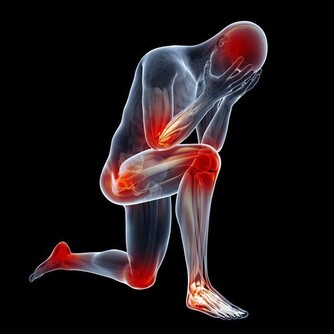

再不改掉就「屎定了」! 隨著人們對於生活享受的追求,生活中種種的設備也都越來越便利。單單是廁所就已經從以往的蹲廁發展到如今處處可見的坐廁,除了方便腳力不好的老人家上廁所以外,也可以讓其他人排便時更為舒適。只不過,這看起來很便捷的坐廁對於身體和排洩過程而言真的是理想的設計嗎? ▼如果你有便秘、腸胃炎、痔瘡、甚至是結腸癌的話,很有可能都是因為不正確的排便姿勢說造成的哦!國外資深的微生物學家-茱莉亞(Gulia Enders)指出,如果根據人體的天然構造去分析如廁的課題,大家就會發現其實蹲姿才是人類最為自然的排便姿勢。

▼請大家先回想自己坐在馬桶時的情形,是不是膝蓋和身體保持大約90度的姿勢呢?以坐姿排便時,幫助控便的恥骨直腸肌因為姿勢的問題無法放鬆,從而導致了如廁時的困難;相反地,若是以身體和膝蓋呈現110度的蹲姿排便時,恥骨直腸肌才能完全疏鬆,在一定程度的腹壓幫助下,糞便就能更輕易地從體內排出。

▼有便秘問題的朋友們大部分也會因為不良排便習慣而面對長痔瘡的困擾,有些人只是在排便時輕微出血;但嚴重者分分鐘會因為這小小一顆「痘痘」而痛苦不堪,連行動都成問題。如果你真的不想要因為痔瘡問題去動手術的話,那就趕緊用蹲姿上廁所!